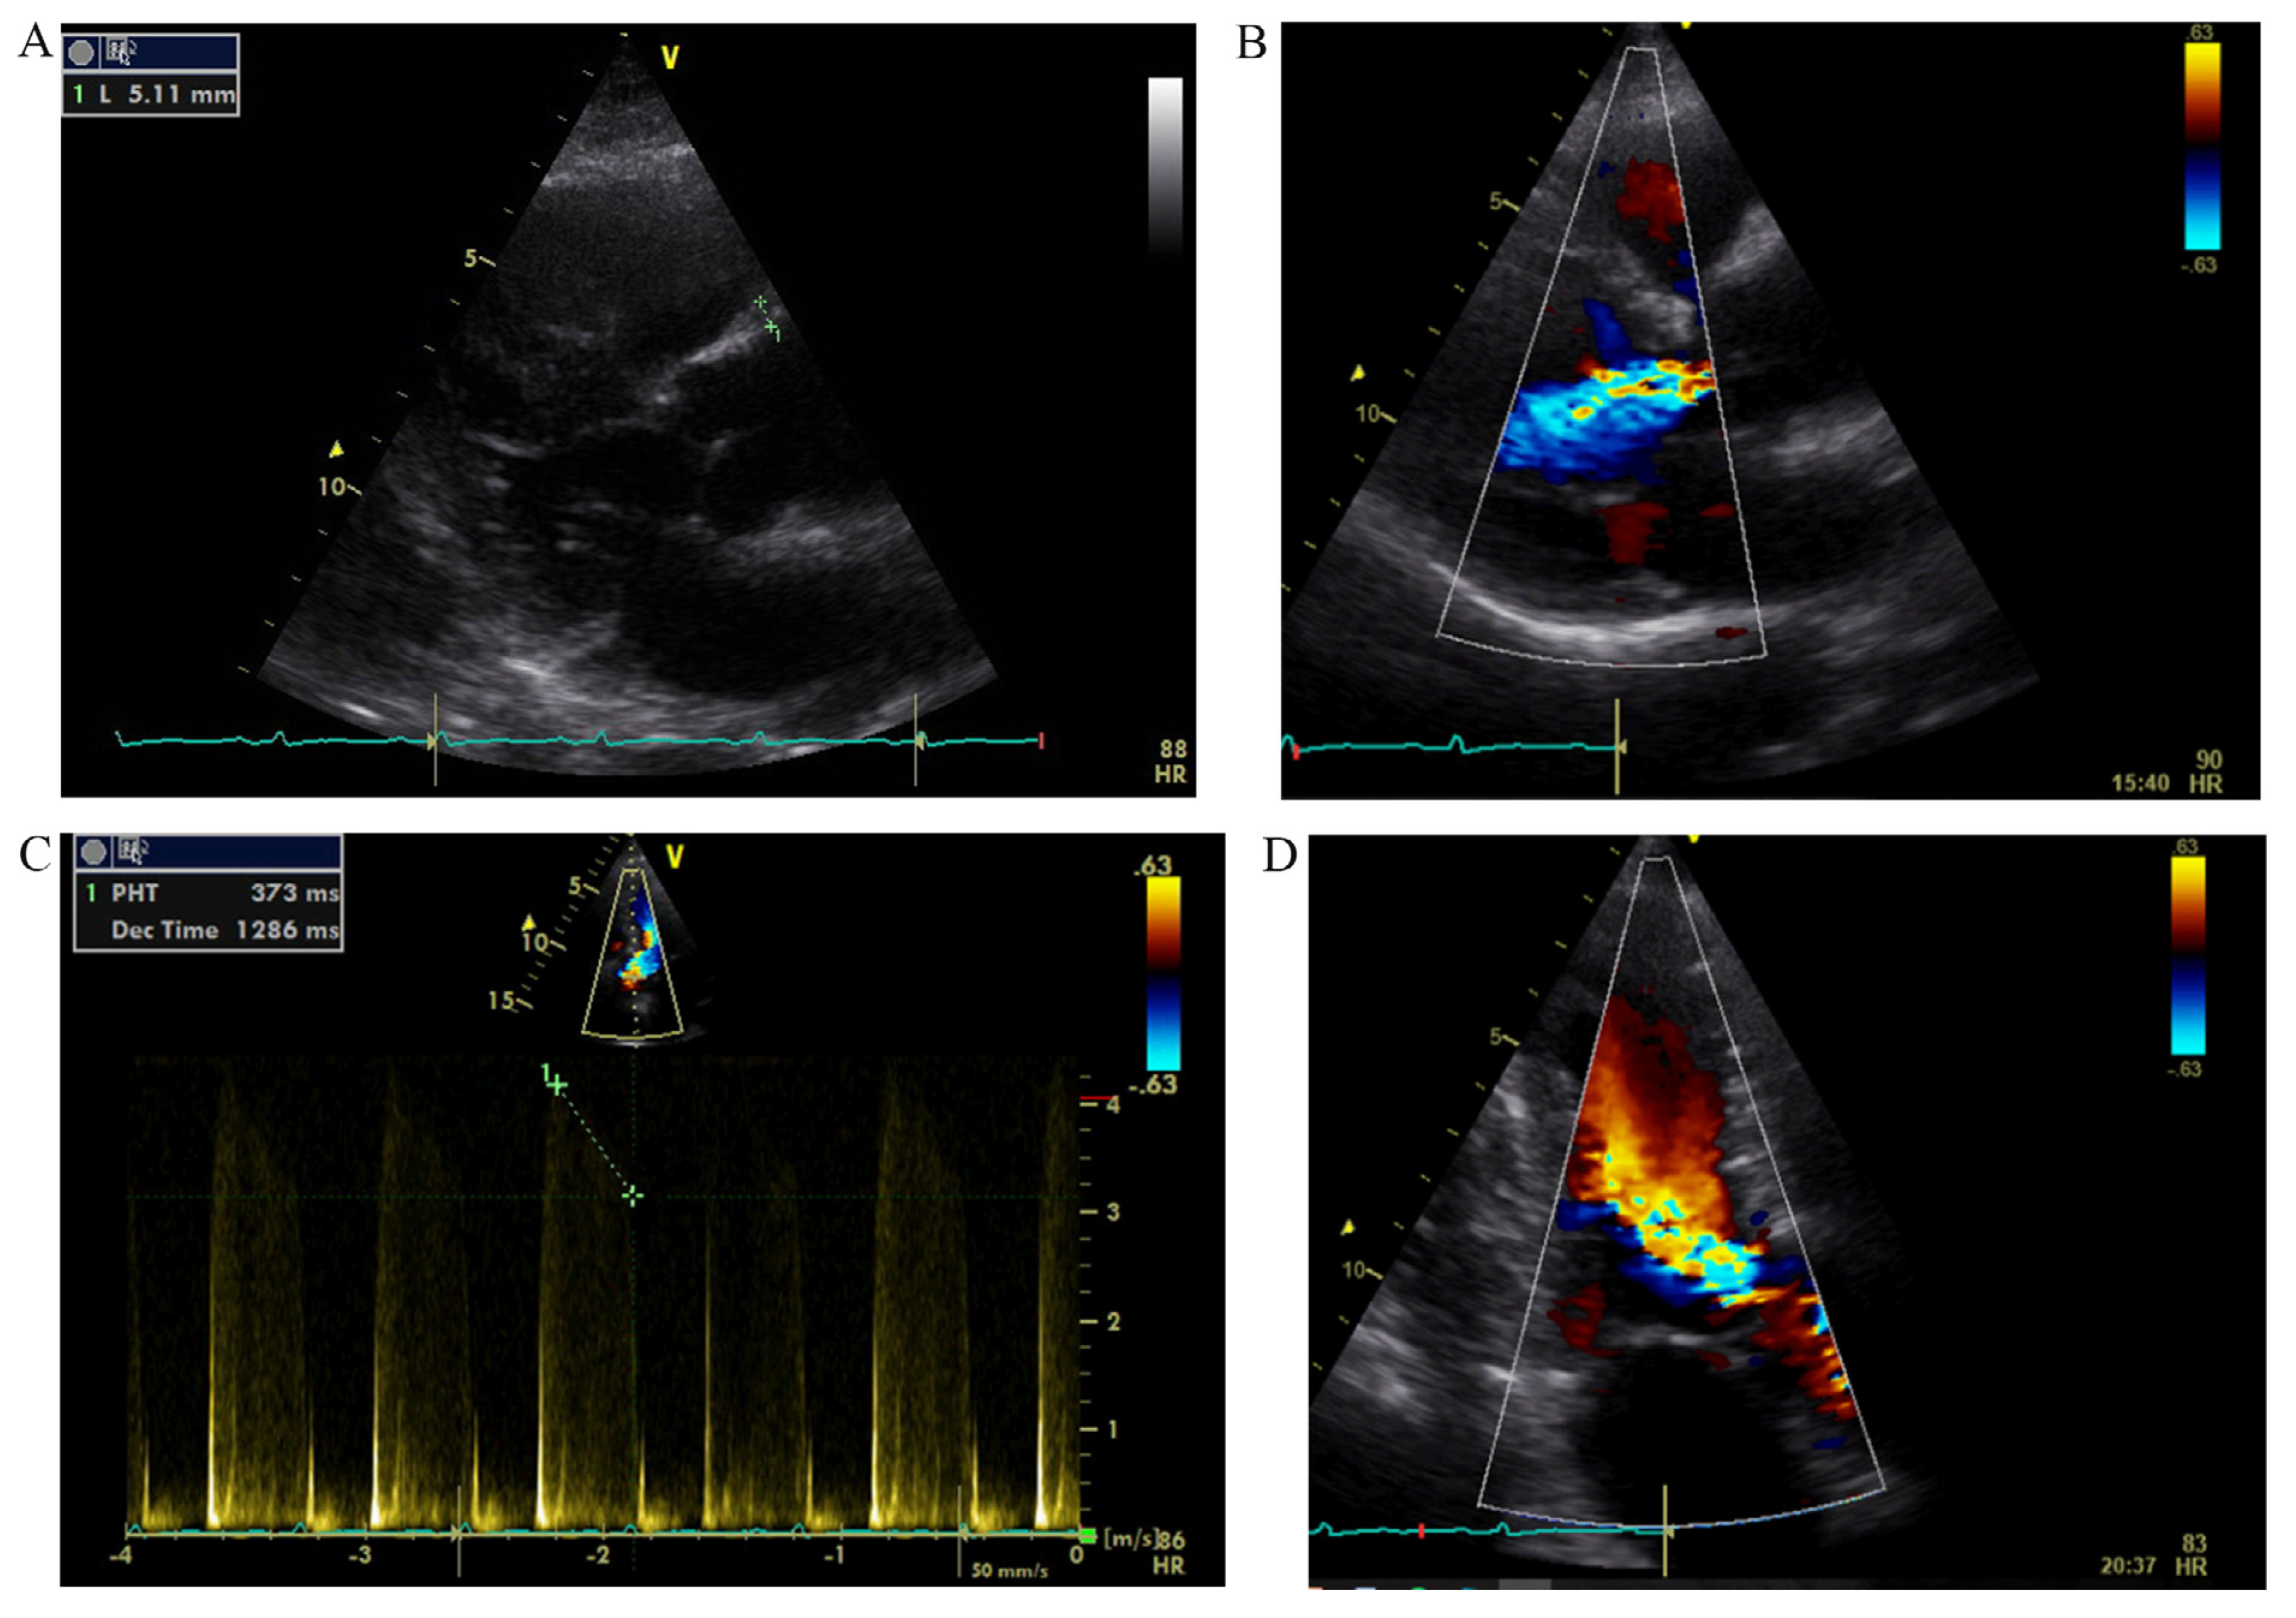

Coronary angiography clarified causes of chest pain: subocclusions of right and left main coronary arteries were found (Fig. 3 and Fig. 4).

Fig. 4. - Right coronary angiogram shows critical ostial stenosis.